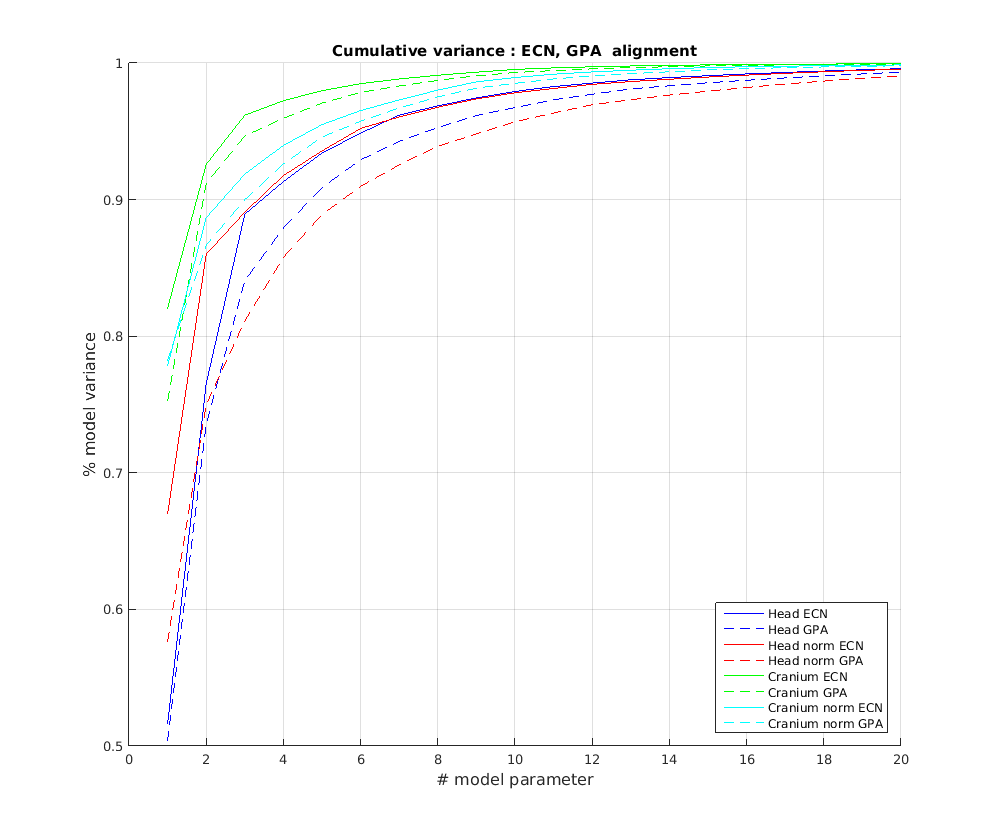

6.2 Model compactness

We evaluate both model construction with geometric alignment (ECN normalisation) and model construction with alignment by Generalised Procrustes Analysis (GPA). Model compactness is a key performance criterion for the correspondence and alignment processes that generate that model [31]. A more compact model has a smaller variance and requires fewer parameters to express a particular shape instance than less compact model. Cumulative variance plots generated by application of PCA are a useful measure of compactness, with more rapidly rising curves indicating more compact models. In Fig. 23 and Fig. 24 we present the cumulative variance plots for our profile models using automatic and manual landmarking respectively and aligned with either ECN or GPA alignment schemes.

Comparing the compactness of the models produced by automatic and manual facial profile landmarking, we found that the performance is almost identical and there is no statistical significance in performance given the modest test size of 100 faces. For example, for the full head profile, with no scale normalisation, the automatic landmarks give cumulative variances of 51.5%, 76.5%, 88.9% and 91.3% over the first four modes whereas the manual landmarks give 50.8%, 76.5%, 88.9% and 91.2%.

A point to note is that whatever model is built, ECN always produces more compact models than GPA. The difference is more marked when a head model is built (cranium and face) compared to cranium only. This can be explained by the fact that the cranium has 210 points sampled on its surface, whereas the face has 128. ECN focusses on aligning the majority group (cranial points) and does not allow more extreme features (such as a large nose) to influence this. GPA on the other hand does, so relatively few points around the nose region can influence alignment over the whole cranium. ECN normalisation is more appropriate when we are interested in cranial shape.